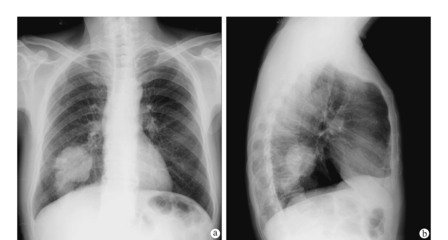

刘某某 男 67岁

2013年8月确诊为原发性肝癌,行手术治疗。

2014年4月16日在家人的搀扶下来到国力医院中医门诊治疗,冉明教授接诊,患者主要症状有:疲乏,胸闷不舒,脘腹、胁肋部胀闷,腰痛,双下肢浮肿,不思饮食。舌淡暗,苔白腻,脉弦细。冉明教授诊断为:肝脾不调,痰湿内停。用中医“状态疗法”对症疏肝健脾,化痰利水治疗。开方1个月,让患者带药回家治疗,并嘱咐患者心情要好,按时服药。

2014年5月28日患者来复诊,仍有疲乏,腰酸的症状,双足水肿,食欲一般,食后腹胀,二便正常。舌淡暗,苔白,脉濡。冉明教授辨证为气血亏虚兼阳虚,痰瘀互阻。以中医“状态疗法”益气养血温阳,祛瘀化痰。鼓励患者坚持治疗可以带瘤生存。患者继续服药至今,目前身体情况基本稳定,定期复查,各项指标都趋向稳定正常水平。